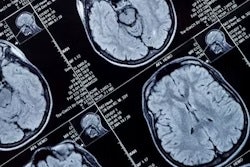

The new agreement now allows GE to offer MAGiC Neuro, a neuroradiology system that generates tissue volumes, myelin-correlated volumes, and quantitative data of the patient.